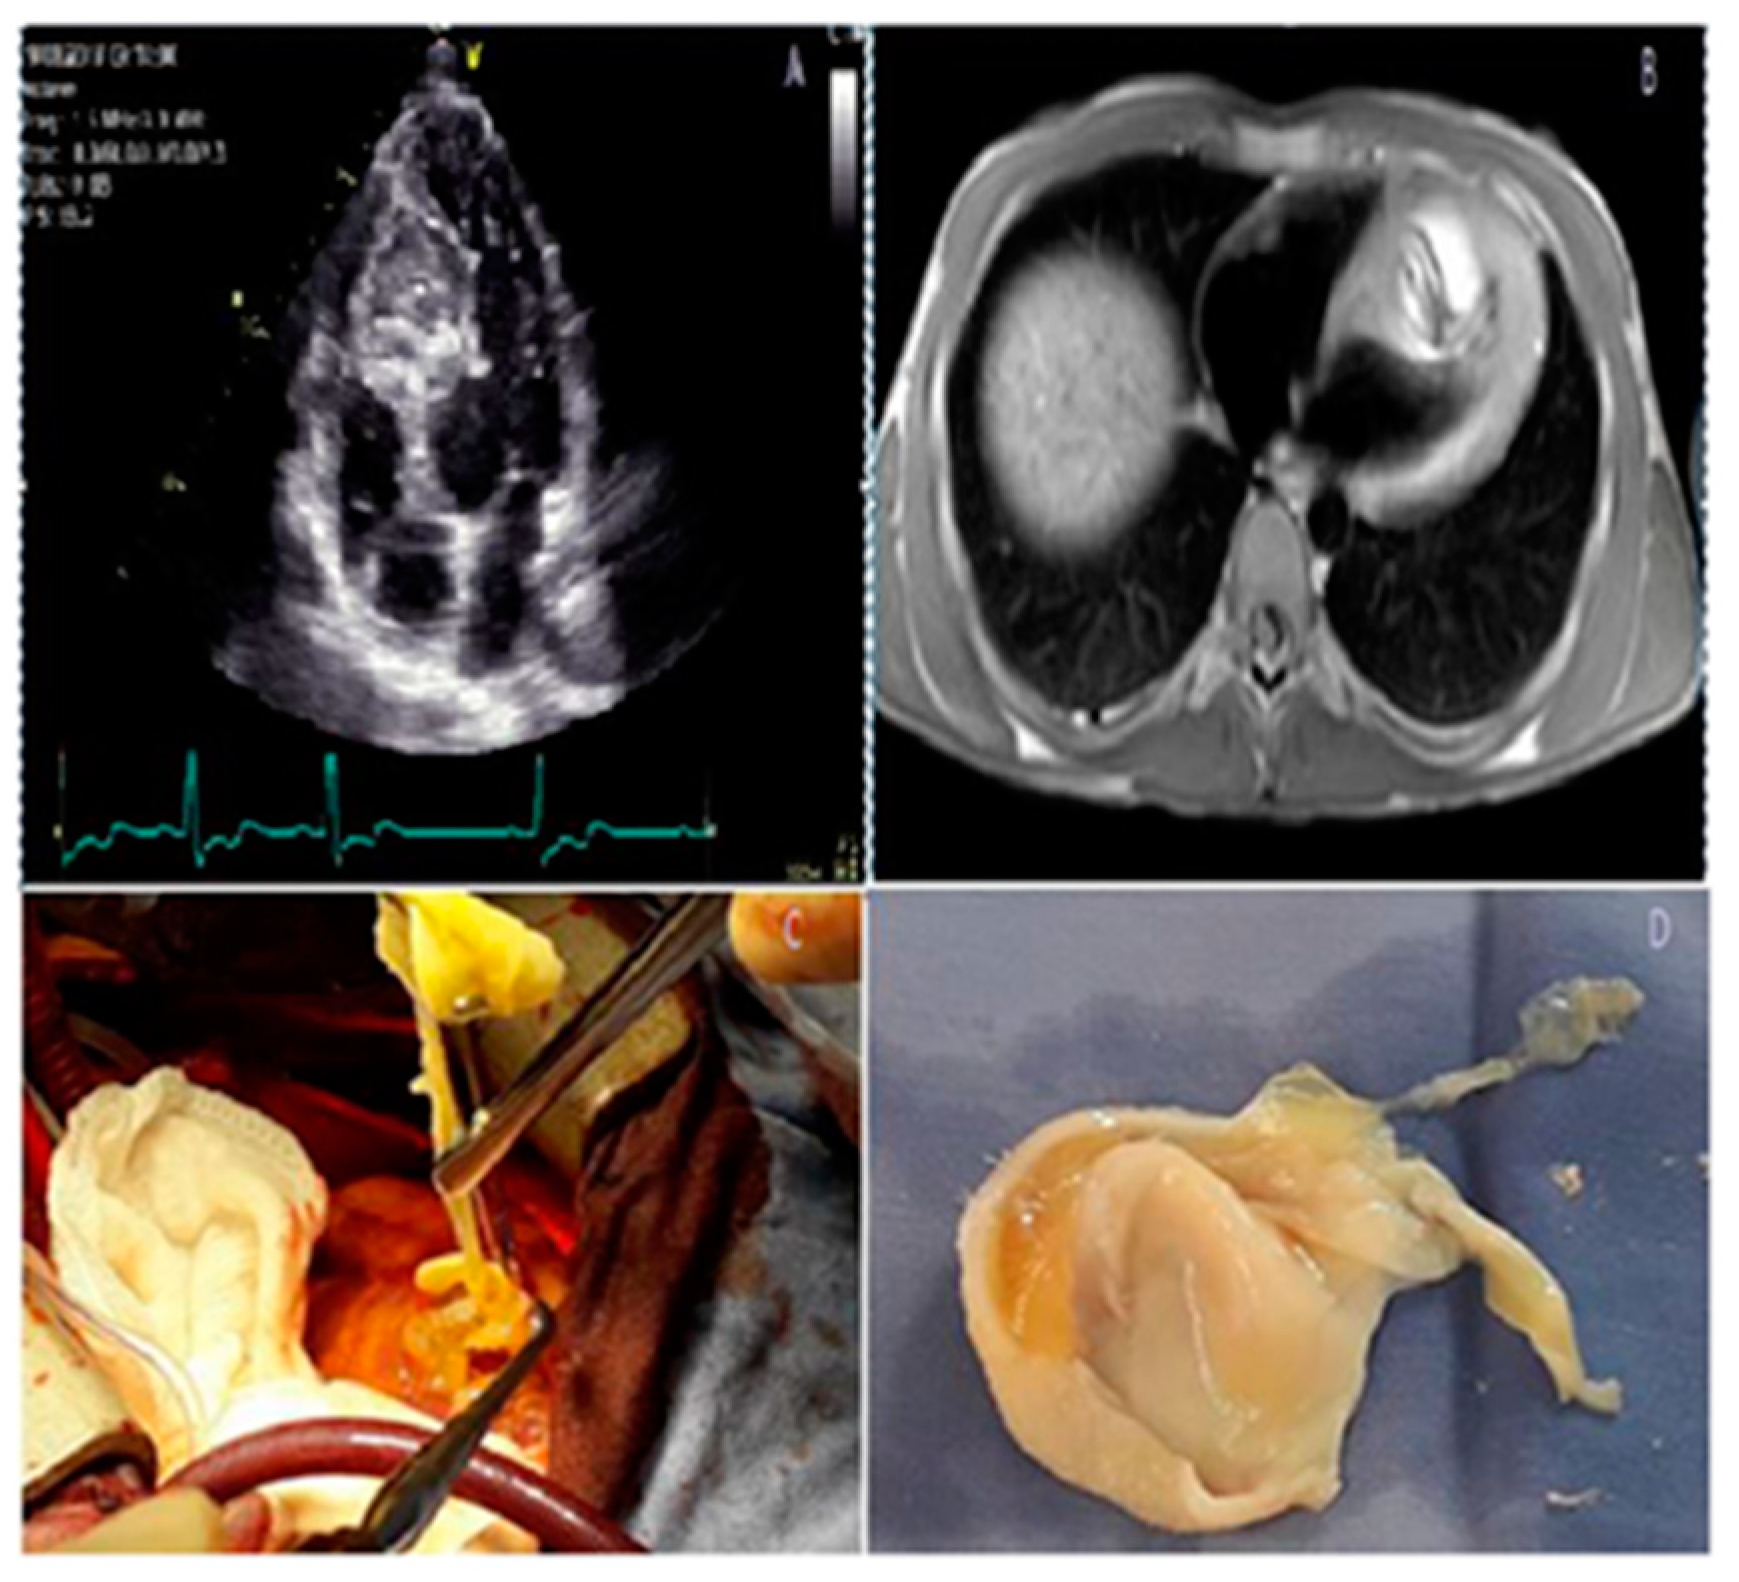

- Stéphant, E.; Anac, S.; Philippeb, D. Inter-ventricular septal cardiac fibroma in an adult: MR and MDCT features with pathologic correlation. Eur. J. Radiol. Extra 2008, 67, e103–e106. [Google Scholar] [CrossRef]